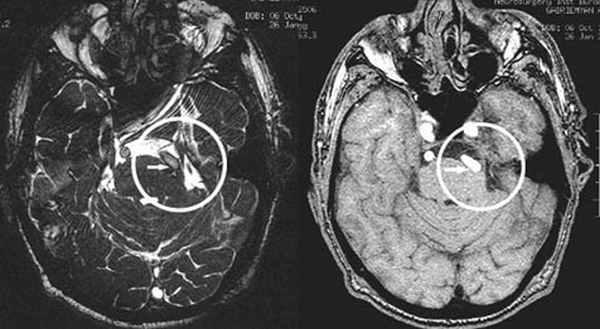

(Слева) При аксиальном исходном изображении (МРА) у пациента с спазмом правой половины лица визуализируются извитая правая позвоночная артерия и ЗНМА, воздействующие на область выхода корешка лицевого нерва. В цистерне мостомозжечкового угла (ММУ) визуализируется лицевой нерв.

(Справа) При аксиальной МРТ CISS на уровне цистерн ММУ у пациента с правосторонним гемифациальным спазмом определяется петля ЗНМА, смещающая ЧН VII в цистерне ММУ кзади, в результате чего он «свешивается» с заднего края слухового отверстия.

(Слева) При аксиальной МРТ CISS у пациента с левосторонним гемифациальным спазмом визуализируется петля левой позвоночной артерии, выдающаяся в цистерну ММУ, где она воздействует на проксимальную часть лицевого нерва в области выхода корешка.

(Справа) При аксиальной МРТ Т2 ВИ у пациента с гемифациальным спазмом определяется долихоэктазия позвоночной артерии, воздействующей на зону выхода корешка лицевого нерва во внутренних отделах цистерны ММУ. Приблизительно у 50% пациентов с гемифациальным спазмом обнаруживаются изменения на МРТ, обычно на тонкосрезовых Т2 последовательностях или МРА.